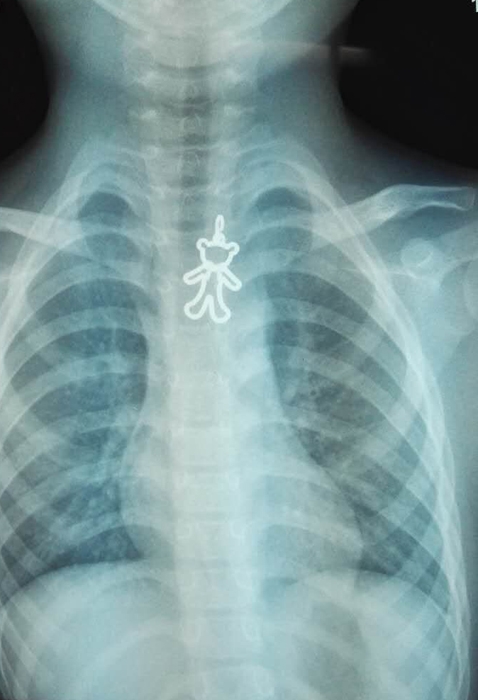

??? 緊急處理無效,老師趕緊聯(lián)系了彤彤家長并把小彤彤送到了附近的醫(yī)院。經(jīng)拍片檢查,小彤彤的食道里卡著一枚小熊模樣的異物。在當(dāng)?shù)蒯t(yī)院的建議下,下午2:30左右,彤彤被轉(zhuǎn)到衢州市人民醫(yī)院耳鼻咽喉科治療。

??? 半個(gè)小時(shí)左右,這枚讓人揪心的金屬小熊被內(nèi)鏡室醫(yī)生順利取出,金屬小熊寬約2CM,高約4-5CM。